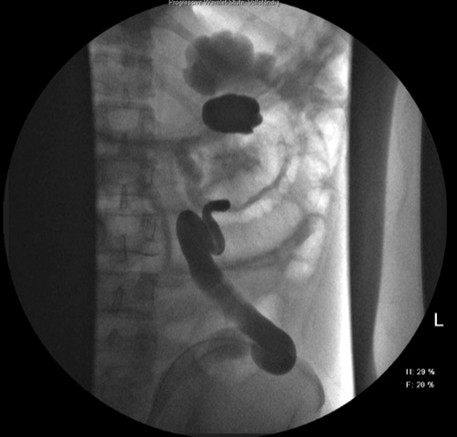

Therapeutisch erfolgte eine Urethrozystoskopie, retrograde Uretropyelographien mit Single-J-Anlagen bds. (links nach Freiresektion des Ostiums (TURB). (Abbildung 1 [Abb. 1] & Abbildung 2 [Abb. 2]). Eine offen-chirurgische Liporesektion blieb ohne operativen Erfolg, sodass bei fortbestehenden Ektasien eine Kontroll-Szintigraphie eine abnehmende Gesamtclearance (links: 66%, rechts: 34%) zeigte.